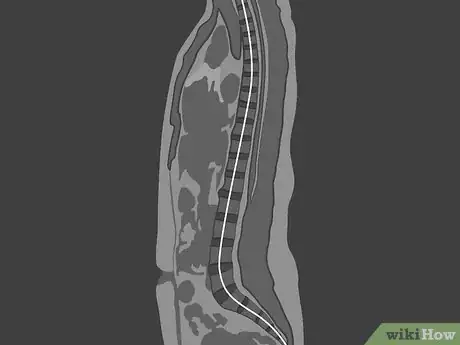

2Identify the type of MRI used in each image. At a minimum, you'll have a sagittal lumbar MRI, which is a vertical image that looks at your spine from the side. You may also have axial images, which look at a cross-section of an individual disc. Think of these as similar to slicing a tree log in sections to look at the rings on the tree. Each of these uses one of two imaging techniques:[3]

Tip: If you see a bright, white line running down your spine on a sagittal MRI, you're looking at a T2-weighted image. The white line is the cerebrospinal fluid of your spinal canal, which holds your nerves.

- It's easier to see this if you're looking at a T2 image, in which the spinal canal will be a bright white compared to the rest of the image.